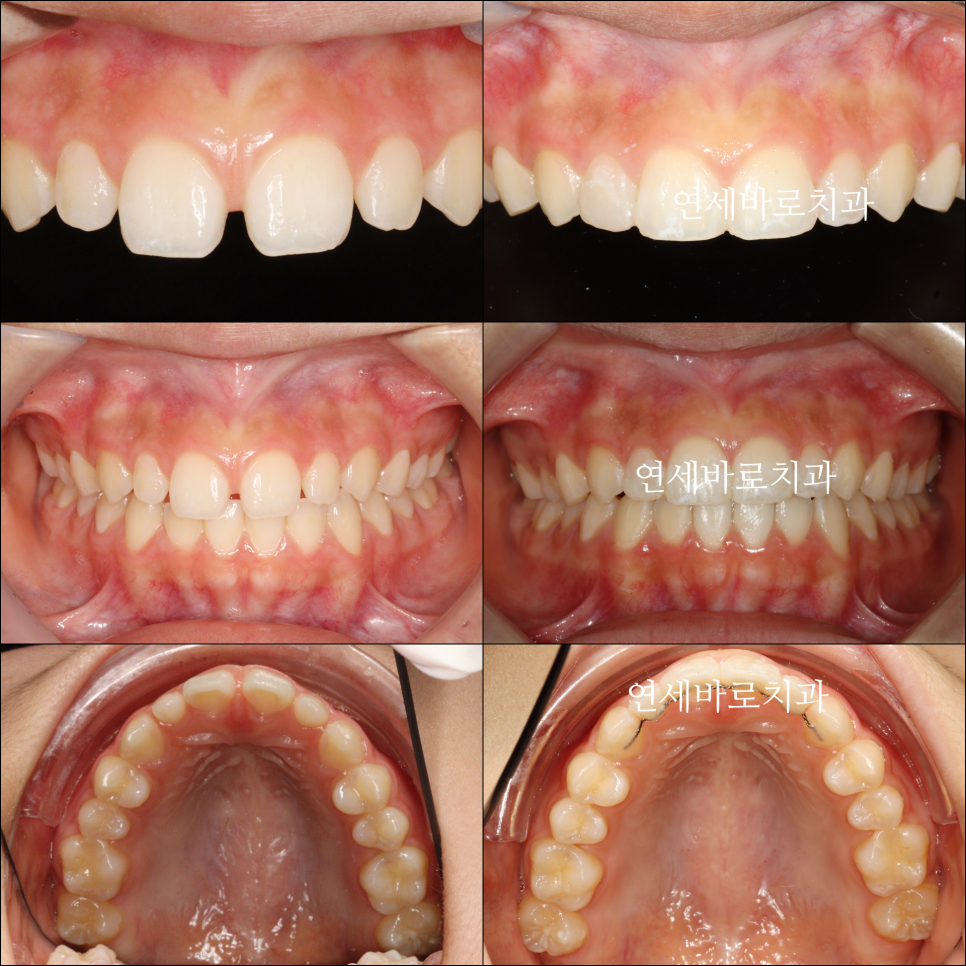

1월에 왔던 아이입니다. 어금니 교합은 너무나 좋아서 건들일것이 없었어요

처음 치료를 시작한 날의 모습입니다.

치료가 끝난 당시 모습입니다.

최종적으로 아이는 레진으로 임시로 공간을 매꾸기로 했습니다.

하지만 인비절라인라이트는 치료 범위는 부분교정과 비슷하지만

사실상 전체교정으로 중심선도 맞출 수 있답니다. (모든 환자분들께 적용되는 것은 아닙니다)

이 환자분도 중심선을 맞추기 위해 고무줄을 함께 사용했습니다.